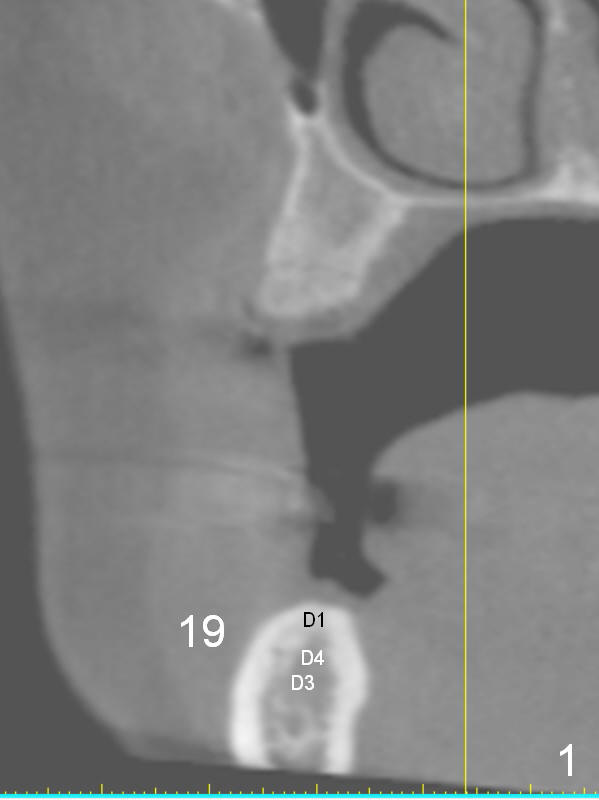

A 49-year-old lady is petit.  The crest at #30 is narrow.  A small implant is placed.  To increase its longevity, the patient should have left 1st molar occlusion.   Bone density at #19 is D1 (the cortex), D4 (upper medulla) and D3 (lower medulla) (Fig.1).  Bone is wide enough to hold a 6 mm (in diameter) implant, but a 8 mm long implant appears to be too long (Fig.2).  Therefore, a 6 or 6.5x6 mm implant appears to be appropriate (Fig.3).  How about the bone at #14?